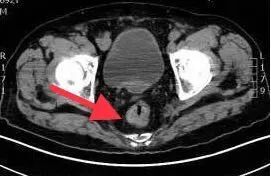

影像照片